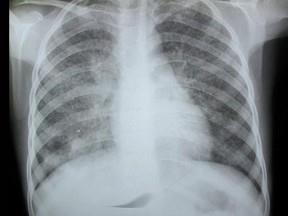

问题 女,12岁,咳嗽、低热2月余,结合胸片,最可能的诊断是?(?)

选项 A.血行播撒型肺结核 B.两肺含铁血黄素沉着 C.间质性肺炎 D.支气管肺炎 E.风心二狭

答案 A